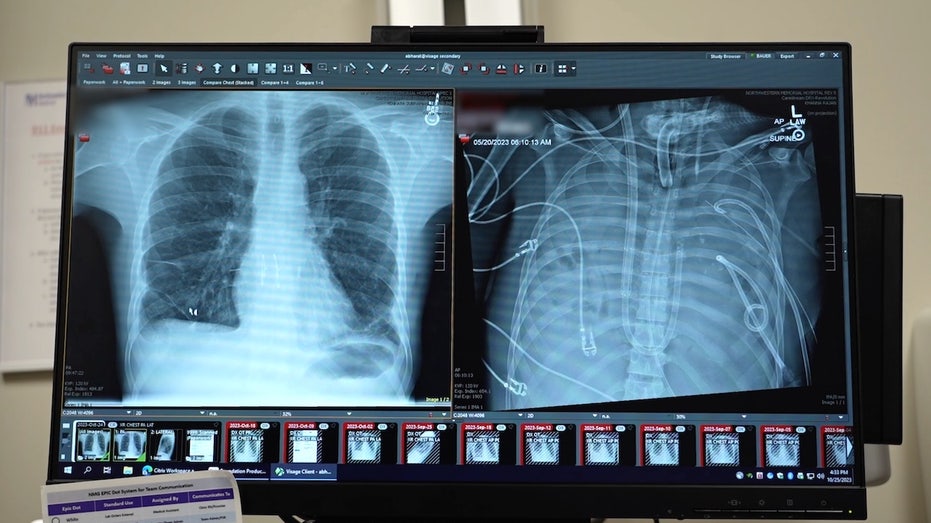

Surgeons at Northwestern Medicine in Chicago were able to keep a critically ill patient alive for 48 hours after removing both of his lungs, the hospital reported last week.

The patient, a 33-year-old Missouri resident whose name was not shared, was originally flown to Northwestern Memorial Hospital with lung failure linked to a flu infection in spring 2023.

In a case study, which was published last week in the Cell Press journal Med, experts revealed a “molecular analysis” of the removed lungs, showing extensive scarring and damage. This supports the idea that in some severe cases of acute respiratory distress syndrome, transplantation may be the only viable option.